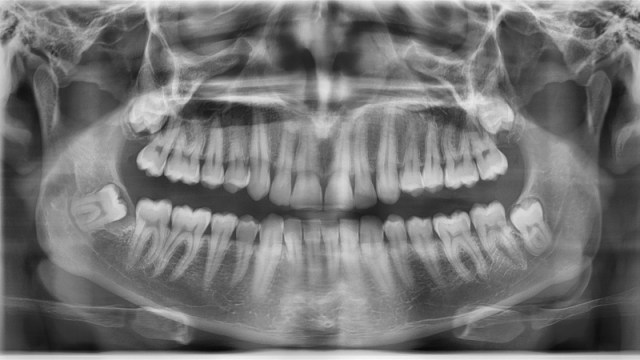

The Singing Dentures Of Manchester And Other Places